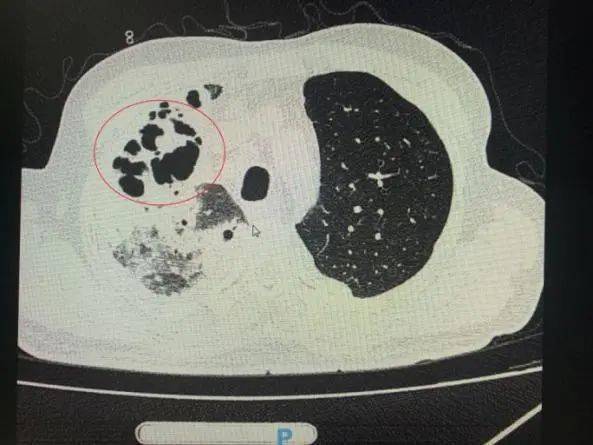

番禺院区呼吸内科何梦璋主任接诊后 , 对钟叔进行详细检查 。 此时 , 钟叔的病情已经十分危急 , 由于不能自主呼吸 , 他带上了无创呼吸机辅助呼吸治疗 。 看到钟叔胸片时 , 医护人员头皮也一阵发麻 , 胸部CT可见双肺多发的炎症浸润、双肺多发空洞 。 通俗来说 , 钟叔的肺部已经被病原体蚕食 , 啃出无数个大小各异的洞!可怕的是 , 这种病变对肺功能的破坏是永久性、不可恢复的 。 根据钟叔病史以及胸部CT结果 , 最终诊断为“吸入性肺脓肿” 。

钟叔的肺部被病原体蚕食 , 啃出无数个大小各异的洞 。